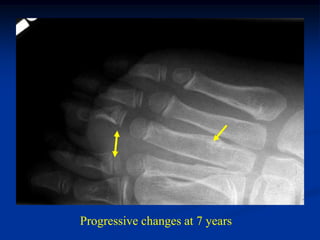

CLASSIC        Case #254

2 month male with infantile fibromatosis right leg

AP                       LAT

Dysplastic bowing fibula at age 2 years

Progressive changes at 7 years